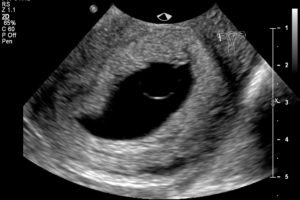

При помощи УЗИ гинеколог сможет увидеть не только угрозу, но и ее возможную причину (аномалия развития плода, предлежание и отслойку плаценты, признаки внутриутробного инфицирования, нарушение кровотока). При ультразвуковом исследовании всегда можно оценить состояние малыша и если потребуется, принять все возможные меры по сохранению беременности и спасению жизни плода.

Доктор произведет осмотр, во время которого оценит состояние матки и шейки матки, а также назначит УЗИ для оценки состояния плода.

Именно поэтому после того как случился выкидыш обязательно необходимо выполнить контрольное ультразвуковое исследование органов малого таза, чтобы убедиться в отсутствии в матке тканей плода. Если они были обнаружены, то потребуется выполнение гинекологической чистки.